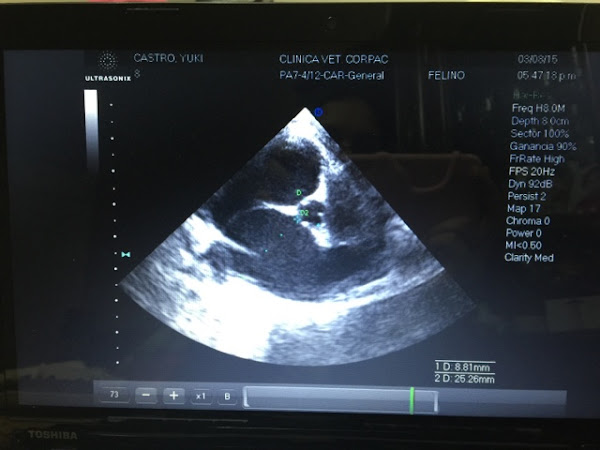

Inmediatamente nos dirigimos al mejor cardiólogo de mi ciudad y después de evaluarlo, revisar los anteriores resultados, sacarle una placa y ecocardiograma, concluyó con el siguiente diagnóstico que a continuación detallo:

Mi Yuki ... Cardiomiopatía hipertrófica severa con dilatación biatrial severa y éstasis sanguíneo secundario. Fibrosis subendocárdica.

Ecocardiograma

Las piernas me temblaban, las manos me sudaban, mi corazón palpitaba tan fuerte que parecía se iba a salir de mi pecho; finalmente me llené de valor y mientras el doctor hablaba y explicaba las imágenes que mostraba el ecocardiograma me atreví a preguntar...